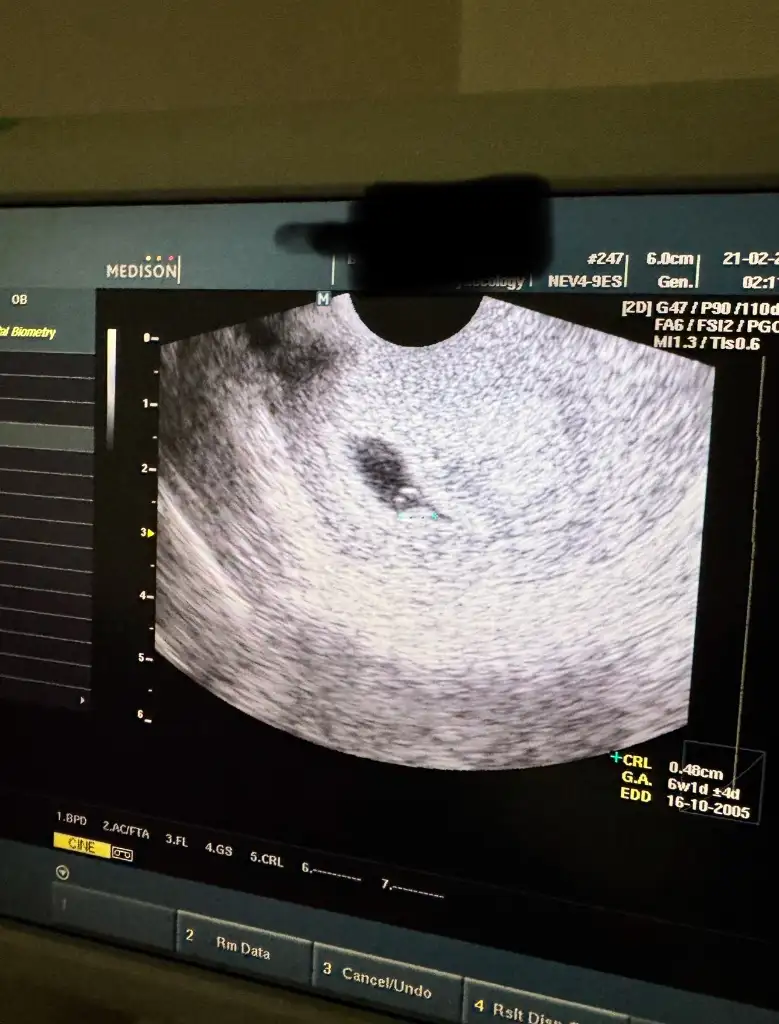

Kalp atışını duyduk . Rabbim isteyen herkese nasip etsin💕

Eklentiler

• IMG_9683.webp

IMG_9683.webp

46,9 KB · Görüntüleme: 60